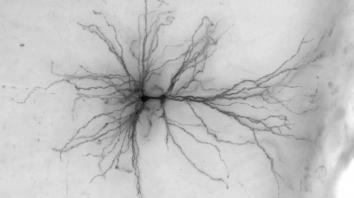

脑科学突破进展 计算机虚拟可活动人脑神经细胞模型数世纪以来,科学家对大脑奥秘的了解仍然十分有限。艾伦脑科学研究所的科学家取得了突破性神经科学研究成果,通过大数据计算机创造出了活动的虚拟脑神经细胞模型,该研究能够使今后对人脑和器官的探究过程更加便利和深入。这项计算机模拟人脑神经细胞3D模型能够虚拟活体人脑细胞运作,其基于外科手术团...